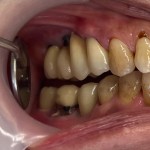

重度歯周病患者の選択肢が少ない中での審美歯科治療、歯周病治療、入れ歯治療

都内在住の患者さんです。

全体の歯が揺れていて、数年前のインプラントが自然に抜けてしまい、かかりつけの歯医者で歯周病がかなり進んでいると言われ来院された患者さんです。

口の治療にはかなりのお金を使っているとの事でデンタルIQも高かったですが、歯周病治療に意識は高かったわりに治療がないがしろにされていた様に思われます。

10年前に入間市の私のクリニックに来られれば、違った結果になったのではないでしょうか。

いずれにしても、今後の治療方針、治療計画が重要なのです。

入れ歯にしたくない、前の歯も後ろの歯もインプラントで支台歯(土台の歯)には使えない、重度の歯周疾患である等。

問題点はまだまだありますが、難しい話になるので、今回は控えます。

患者さんと十分なインフォームドコンセントをし、審美歯科治療、ポンティック(ダミー)を付けたジルコニアクラウンを選択しました。

患者さんも大変喜んで頂き、良好な結果が得られました。

長期に予後を追っていかなければならない患者さんの一人です。